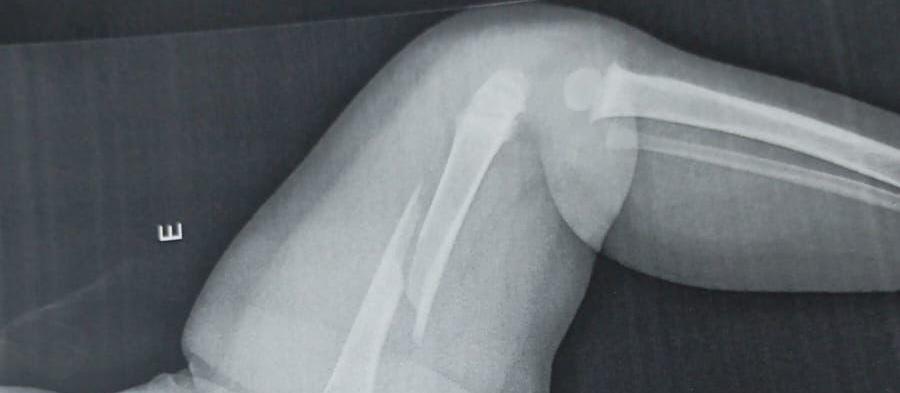

Rosângela Paula Afonso conta como encontrou a criança, que segundo a mãe tinha caído da cama. A suspeita da avó e do pai do bebê é que Benjamin, de um ano e cinco meses, vinha sofrendo agressões: “o médico disse que ele tinha uma fratura antiga no bracinho”. O caso será investigado pela delegacia de Polícia Civil de Paiçandu.

Benjamin estava com as pernas inchadas e roxas e sentia dor.

No hospital, os médicos constataram que o fêmur da criança estava fraturado.

Os médicos disseram que a criança também tem uma fratura antiga. [ouça o áudio]